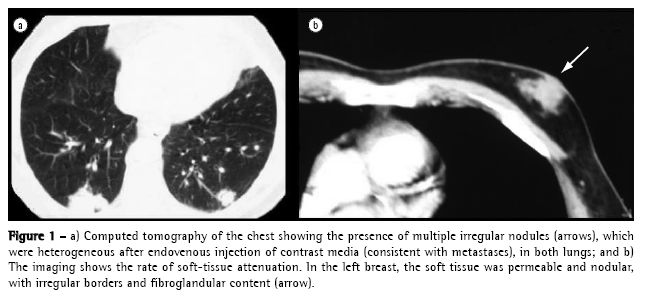

Chest X-rays showed multiple nodules in both pulmonary fields consistent with metastases, which were confirmed through tomographic study. In addition to the pulmonary metastases, there was an accidental X-ray finding of a mass consistent with neoplasia in the left breast (Figure 1).

The incidence of pulmonary parenchymal metastases originating from primary extrathoracic neoplasias ranges from 20 to 54%. Metastases originating from solid tumors are the most common causes of multiple pulmonary nodules, accounting for approximately 80% of such cases (Chart 1).(4) Computed tomography scans of the chest are the test of choice for the evaluation of multiple pulmonary nodules. Such lesions are typically smaller than 5 mm in diameter and are found in the subpleural region, although they can occasionally be obscured by the mediastinal structures or by the hemidiaphragm.